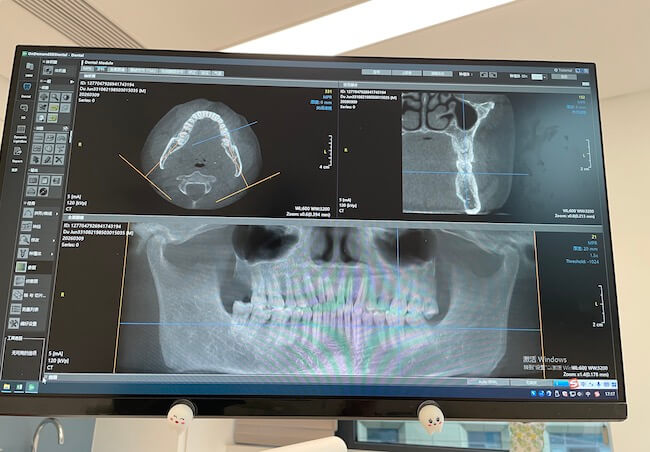

起因是三天前吃一块很硬的肉,嚼半天嚼不动,当时没什么感觉,事后那个位置的牙越来越疼,持续不退。平时生活中难免偶尔会牙疼,但是连续疼几天就要果断去医院了。这次是在上班时临时决定去看牙,就找了离公司近的杭州口腔医院(私立,但是能用医保)。

这次拔的是下牙,比上牙困难很多,所以整个过程耗时更久。在钻牙的时候我能闻到一股烧焦味,是最为恐怖的时刻。好在这个过程中医生不断言语安慰我,极大缓解了我的紧张。